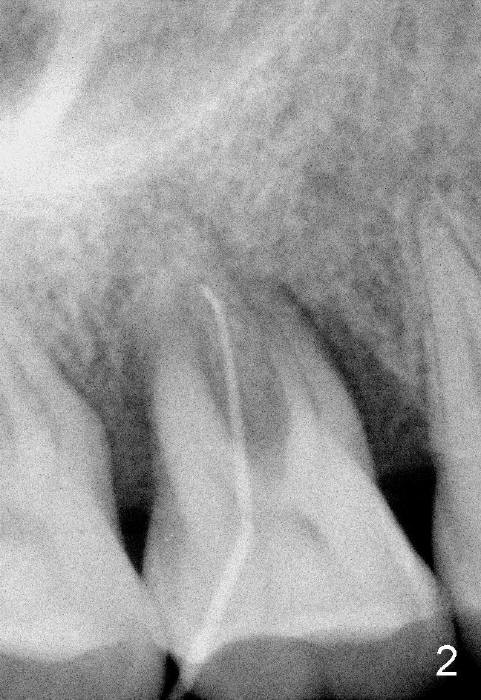

The tooth #3 has severe periodontitis with probably endodontic lesion (Fig.1,2). The patient is a 43-year-old man with apprehension of dentistry. An acute infection causes pain and tooth shift (Fig.4,5). A 7x17 mm immediate implant is planned (Fig.3). The palatal socket is shallow (Fig.6 P), corresponding to severe recessive palatal root (Fig.5 P). The osteotomy is created mainly in the buccal socket (Fig.6 B), exactly in the lingual slope of the septum. Initially osteotomes are used, followed by tap placement (Fig.7 T (4.5x20 mm at the depth of 17 mm). When the implant is placed as planned (Fig.8 I), there is more vertical contact (Fig.8 red line) than that associated with the tap (Fig.7 red line). The corresponding insertion torque is between 50 and 60 Ncm. There is only one small gap buccally, which is filled with bone graft (Fig.9 <). After the insertion of a short abutments with vertical slots (Fig.9,10 A), perio dressing is used to cover the wound. The palatal socket is expected to heal uneventfully (Fig.10 P). In fact, it does in 7 days (Fig.12 P); the bone graft in the mesiobuccal aspect is healing and stabilized (Fig.11 <). By two weeks postop, the mesiobuccal socket has healed (Fig.13 <). With removal of a diseased tooth, our body has amazing power to heal.